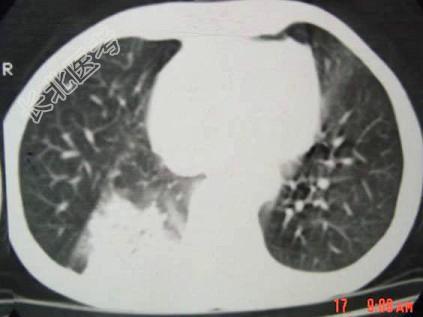

- 单项选择题男,40岁, 胸背疼痛一周,消瘦一月, CT检查如图,最可能的诊断为 ( )

A、右下肺结核

B、右下肺脓肿

C、右下肺炎

D、右下肺肺泡癌

E、右下肺炎性假瘤